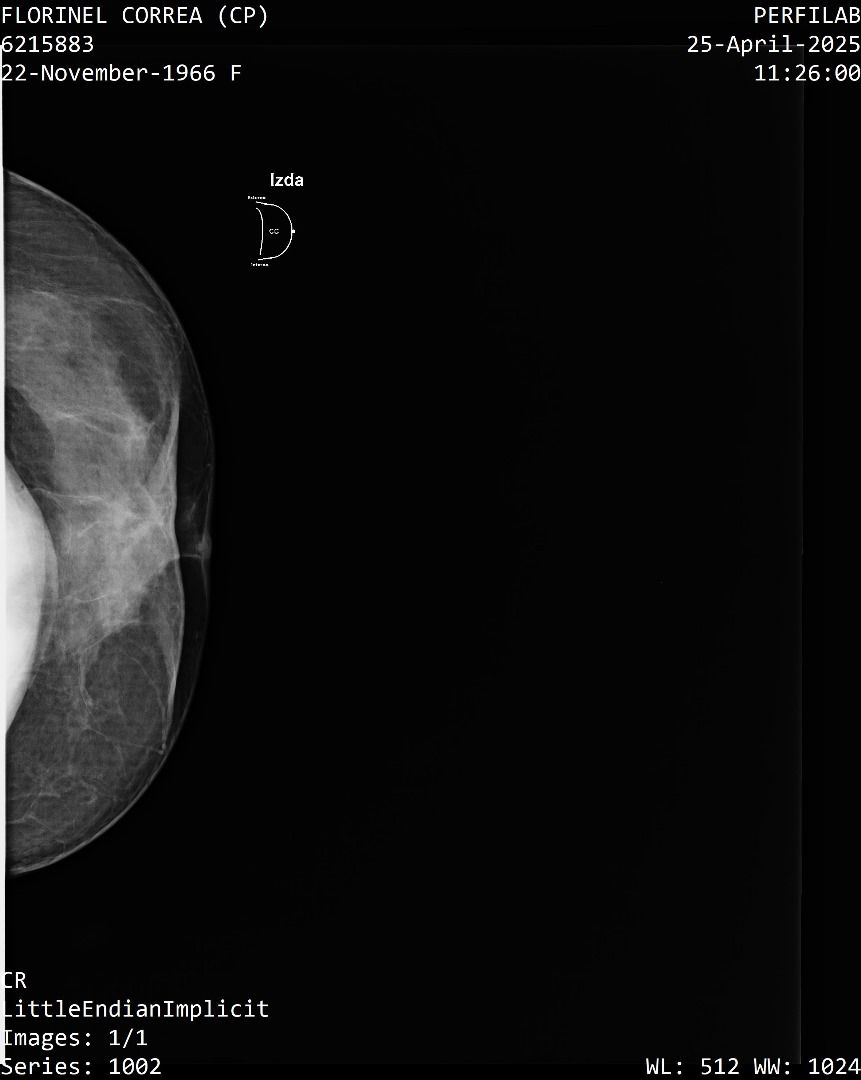

A Correa se le practicó un estudio de mamografía bilateral, la cual reporta una densidad mamaria heterogéneamente densa (ACR C), lo cual puede dificultar la detección de lesiones sospechosas.

Además, la presencia de implantes mamarios limita aún más la visibilidad del tejido mamario.

También se identificó un ganglio linfático de aspecto residual en la axila derecha que se considera sospechoso con este método, requiere evaluación urgente mediante ecografía mamaria.